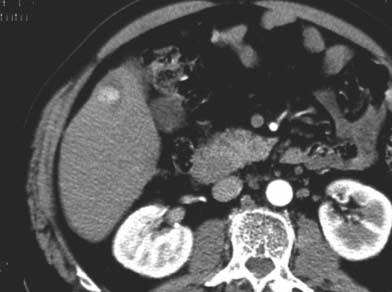

ก่อนทำ

RFA |

หลังทำ